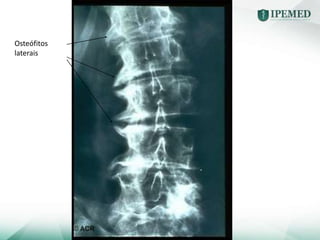

Coluna Normal

Osteoartrose

Osteófitos

laterais